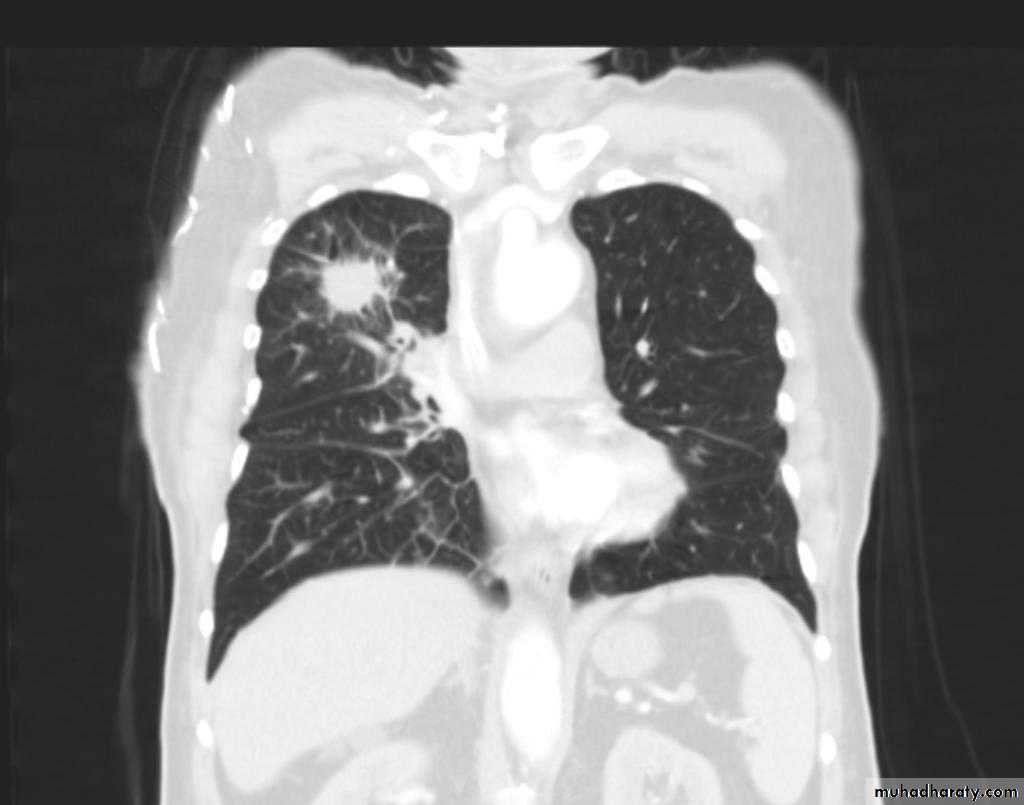

BGCA

70.Bronchogenic CA.

71.BGCA

72.BGCA